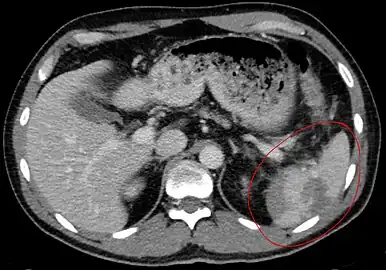

Traumatic rupture of the spleen on contrast enhanced axial CT (portal venous phase) -